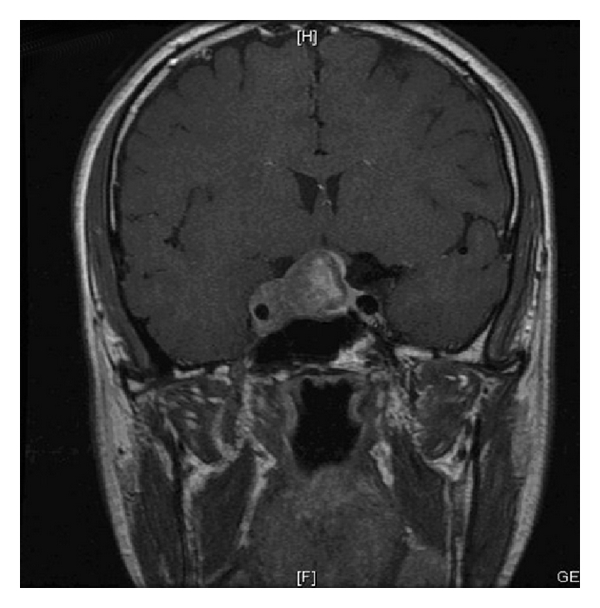

A diagnosis of cluster headache was made and abortive therapy with subcutaneous sumatriptan and high-flow oxygen was given, with no clinical response. Prophylactic therapy with high-dose verapamil did not have any effect on the attack frequency or duration. Given the refractory symptoms, an MRI scan was performed which showed a large pituitary adenoma with right-sided cavernous sinus invasion (Figure 1). The serum prolactin was significantly elevated at 54,700 mU/L (normal range 50–400 mU/L), with normal IGF1 and growth hormone 0.4 mU/L, excluding acromegaly; the remainder of the pituitary function was normal. A pituitary macroprolactinoma was diagnosed and the patient was prescribed cabergoline 0.5 mg twice/week. Over the next four days he described a sensation of parasthesia over the scalp, since which he has not experienced a single headache attack. An MRI scan performed several months later showed significant reduction in tumour volume with resolution of cavernous sinus invasion (Figure 1). Since followup in the endocrine clinic, he has become gonadotropin deficient, requiring testosterone gel replacement, and he remains headache-free with a serum prolactin of 627 mU/L.

(a)

(b)